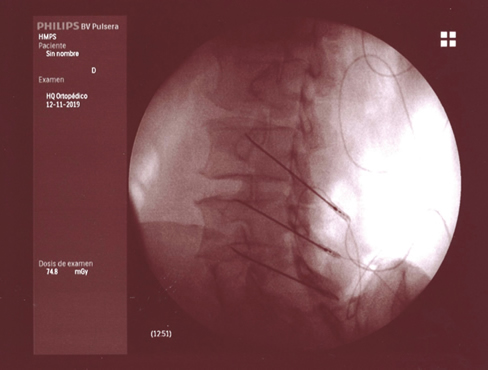

Figura 1